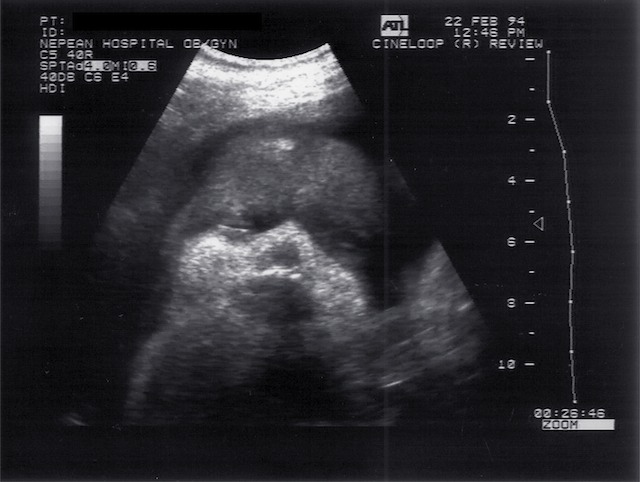

Scans – Obstetric and General